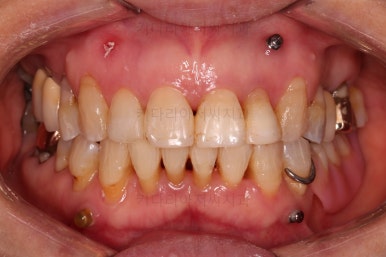

마무리 때의 사진입니다.

교정치료 자체는 9개월만에 끝냈지만 잇몸이 약해서 재발이 우려됐고 예후가 불량해서 뽑아야 되는 치아도 있어 해당 부분을 임플란트를 할 지 최대한 계속 써볼지 등에서 고민하느라 최종 종료는 한참 더 걸리긴 했어요.

부착형 유지장치 뿐만 아니라 보조적으로 재발을 막아줄 목적의 독특한 형태의 뺐다꼈다 유지장치도 드렸어요.(여기서는 공개 안할겁니다. 비밀입니다. ㅎㅎ)

부산부분교정 전후사진을 비교해 볼게요.

치열이 매우 가지런해졌고 보이던 틈새도 다 없어졌으며 뻐드러진 느낌도 완벽히 좋아졌어요.

잇몸에서 쑤욱 빠져나와 보이던 치아도 원위치를 찾았고요.

앞니도 약간이나마 뒤로 들어가서 입매도 많이 좋아졌어요.